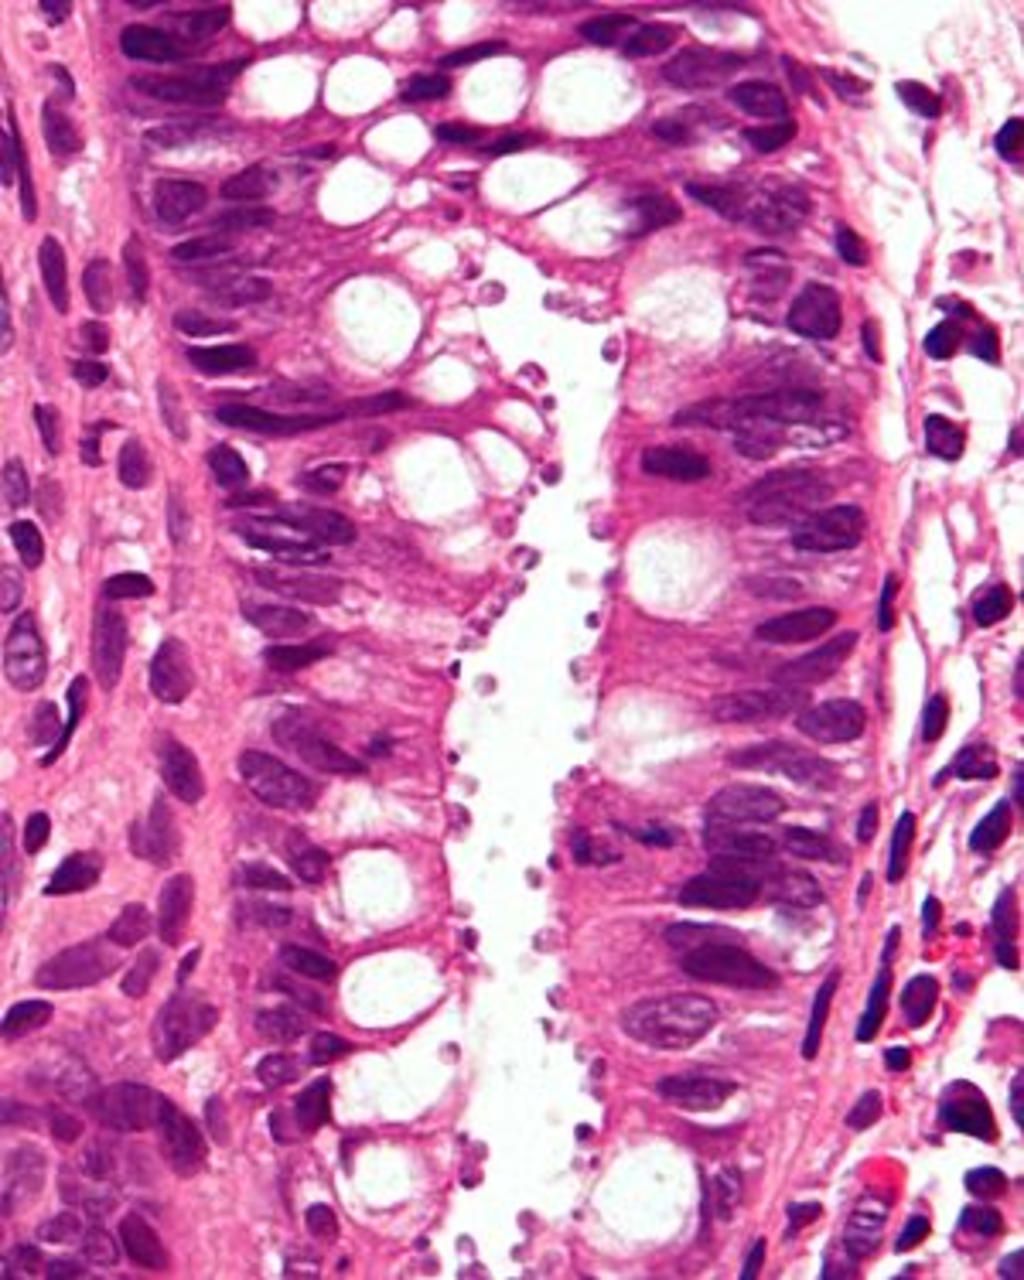

Vì bệnh này được gây ra bởi vi trùng siêu nhỏ ký sinh trùng có tên là bệnh do Cryptosporidium. Có thể tìm thấy Cryptosporidium, hay gọi tắt là Crypto, trong nước, thực phẩm, đất hoặc trên bề mặt hoặc bàn tay bẩn đã bị nhiễm phân của con người hoặc động vật bị nhiễm ký sinh trùng.

– Nguyên nhân lây nhiễm Cryptosporidium đến từ các loài động vật có xương sống như ngựa, cừu, khỉ, mèo, chó và đặc biệt là bò vì là nguồn lây nhiễm quan trọng liên quan đến sự lan truyền bệnh cho con người

– Các loại rau, quả có nang kén hoặc tiếp xúc trực tiếp với động vật cũng là nguyên nhân khiến con người nhiễm loại ký sinh trùng này

– Các loài động vật có vú, một số loại chim non hoặc động vật mới sinh như bê, cừu non, lợn con từ 1-3 tuần tuổi cũng là nguồn bệnh nguy hiểm truyền đơn bào Cryptosporidium